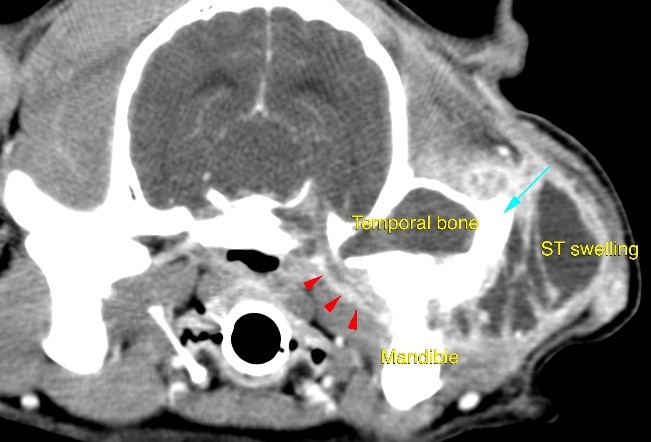

A small tubular structure (red arrowheads), connected the described lesion, with a large and cavitary subcutaneous lesion, that represented the cause of the left sided soft tissue swelling. This lesion was fluid filled and showed a diffuse ring-contrast-enhancement.

Images were highly suggestive of cholesteatoma, a congenital or acquired epidermoid cyst which arise within the tympanic bulla.